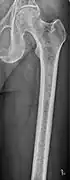

Femur with multiple myeloma lesions -

Same femur before myeloma lesions for comparison -